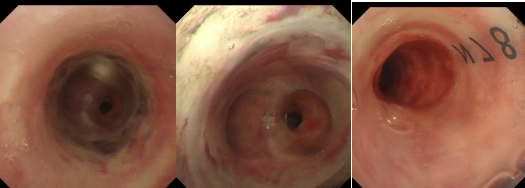

此手术是呼吸内镜介入操作难度极高的手术之一,被称为呼吸内镜介入操作“皇冠”上的明珠。放置“Y”型硅酮支架的难度及风险比普通气管支架要大的多,需要定位准确、一次到位,一旦位置不准确或者支架打不开,会导致患者窒息,带来致命危险。同时在支架置入过程中,需要团队密切配合。最终经广州呼吸健康疾病研究所陈愉教授的指导,我院呼吸内镜中心团队在柴燕玲主任带领下与手术室麻醉团队密切配合成功为患者实施了硬质气管镜置入,呼吸机辅助通气,Nd:YAG激光治疗松解狭窄瘢痕,随后经过球囊扩张处理后,一次性顺利置入Y型硅酮支架。整个过程一气呵成,微调支架位置后支架释放良好,顺利打通生命线,撑起呼吸之门。

气管下段狭窄激光治疗+Y型硅酮支架植入后

术后患者呼吸困难等症状得到了立竿见影的缓解,术后第二天复查支气管镜可见支架在位良好,管腔通畅。大大改善了患者的生活质量,患者于术后第三天下午顺利出院。